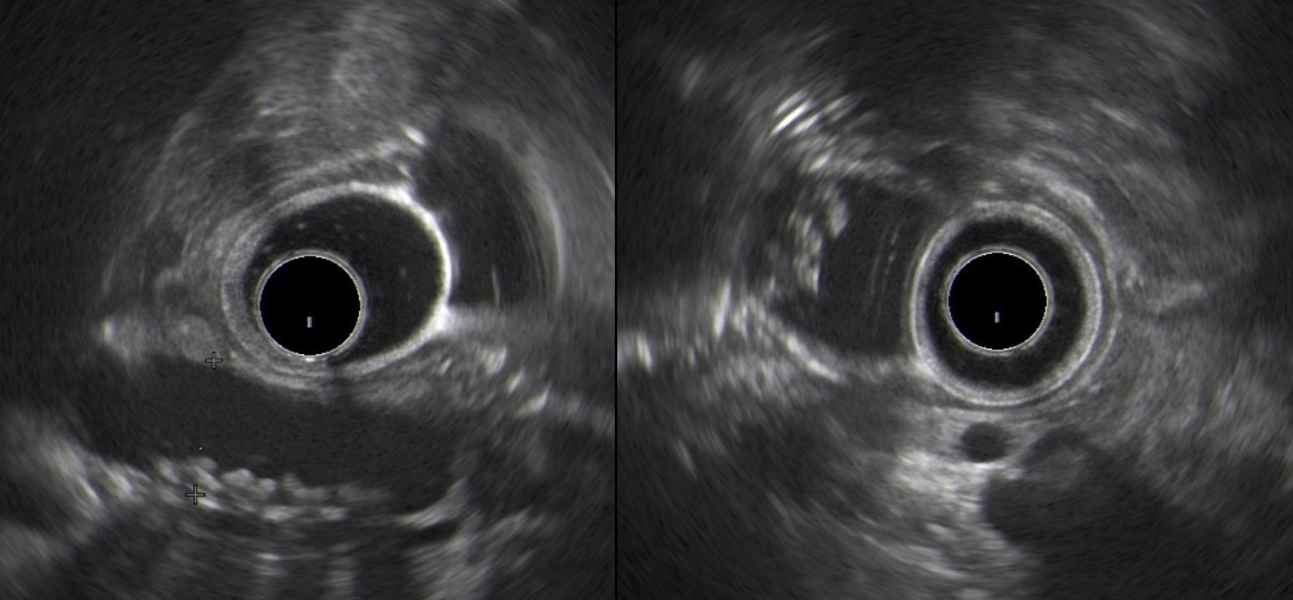

Extensive mediastinal invasion from esophageal carcinoma

Fotografias